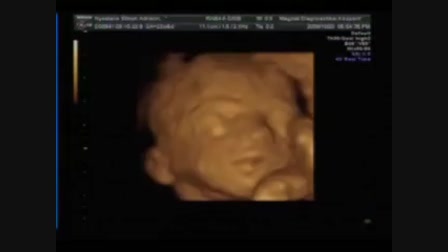

Legfiatalabb informatikusunk

Kíra baba 2009.09.19-én született. A felvétel 2010.01.05-én készült... :-)